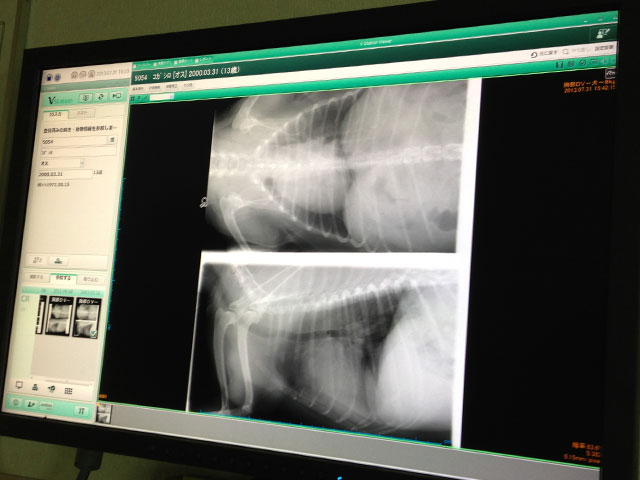

1年くらい前に心音に雑音が聞こえると言われ

なんとなく騙し騙しでやってきたが

一ヶ月前から咳が出るようになったので

病院に行ってレントゲンと血液検査

年齢の事もあるので完治って事はないが

薬を飲めば現状維持になるらしい

痛い出費だが仕方がない